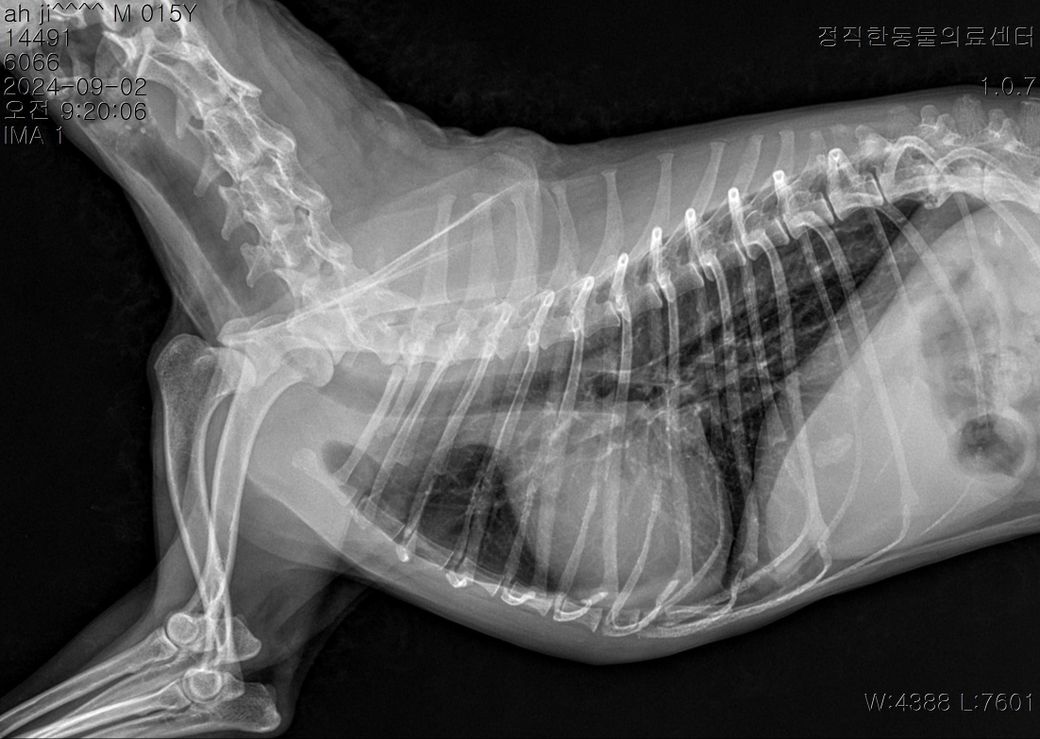

병원에서는 엑스레이상으로나 청진상으로나 폐수종은 아니라고 하더라고요 그런데 왜 이렇게 호흡수가 높은지 60~100까지 갈때도있고 개구호흡 할때도 있습니다 도와주세요...

폐수종으로 볼 근거가 부족한 사진입니다. 즉, 생명에 위해를 줄 수준의 폐수종 양상으로 판단해서는 안되는 사진입니다.

사진상으로도 담석, 신장결석, 디스크 소인들이 있어 보이니 통증이나 염증과 관련한 집중적인 검진을 받으시기 바랍니다.